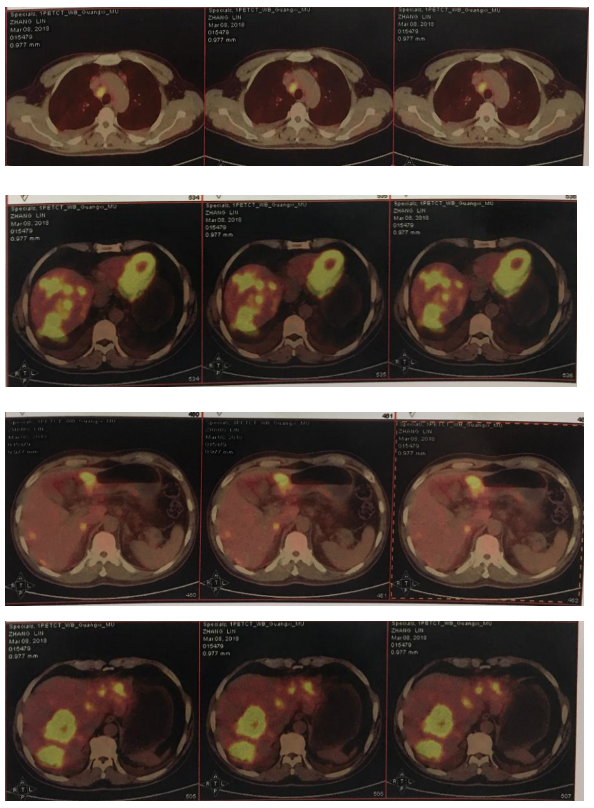

2018-11-19 PET/CT

胃壁代谢稍增高但未见明确的肿物,肝内低代谢结节考虑转移瘤治疗后活性减低,纵膈及右肺门两个淋巴结代谢增高,考虑转移瘤活性尚存、左侧颞骨局部骨质破坏并代谢增高,考虑转移瘤。